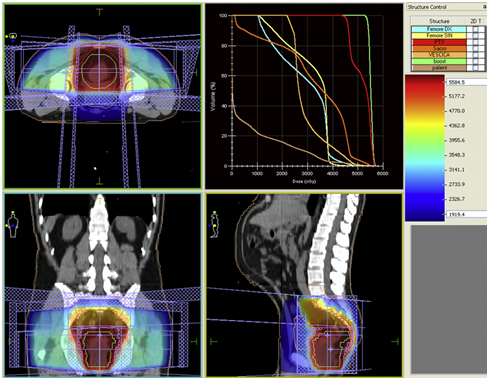

In this way, the design is a three-dimensional treatment and is used for advanced simulation software and computers. In this method, the tumor is positioned with high precision, so the healthy tissue around cancer cells and tumors is far from radiation, and a higher dose can be used to destroy the tumor. This method is most commonly used to treat nasopharyngeal and prostate and liver tumors. In this radiotherapy using the CT scan, the target tissue is simulated virtualistically. This simulation is stored as a digital file on computers and the radiotherapy team can access this file. The physician can then design the treatment with advanced software and check out the tumor position in three dimensions (Figure 2). By this method, the intensity of radiation to the cancerous tissue can be determined with higher precision. This information is stored in the computer and is available to the radiation therapy team. Oncologist specifies a specific treatment for each patient, and the dosimetry and physicist regulate the radiation dose and type of beam. In this method, a virtual simulation session is performed and then the target points are identified with colored tattoos on the patient's body.17–19

Figure 2 Simulation of treatment by Method 3DCRT.19